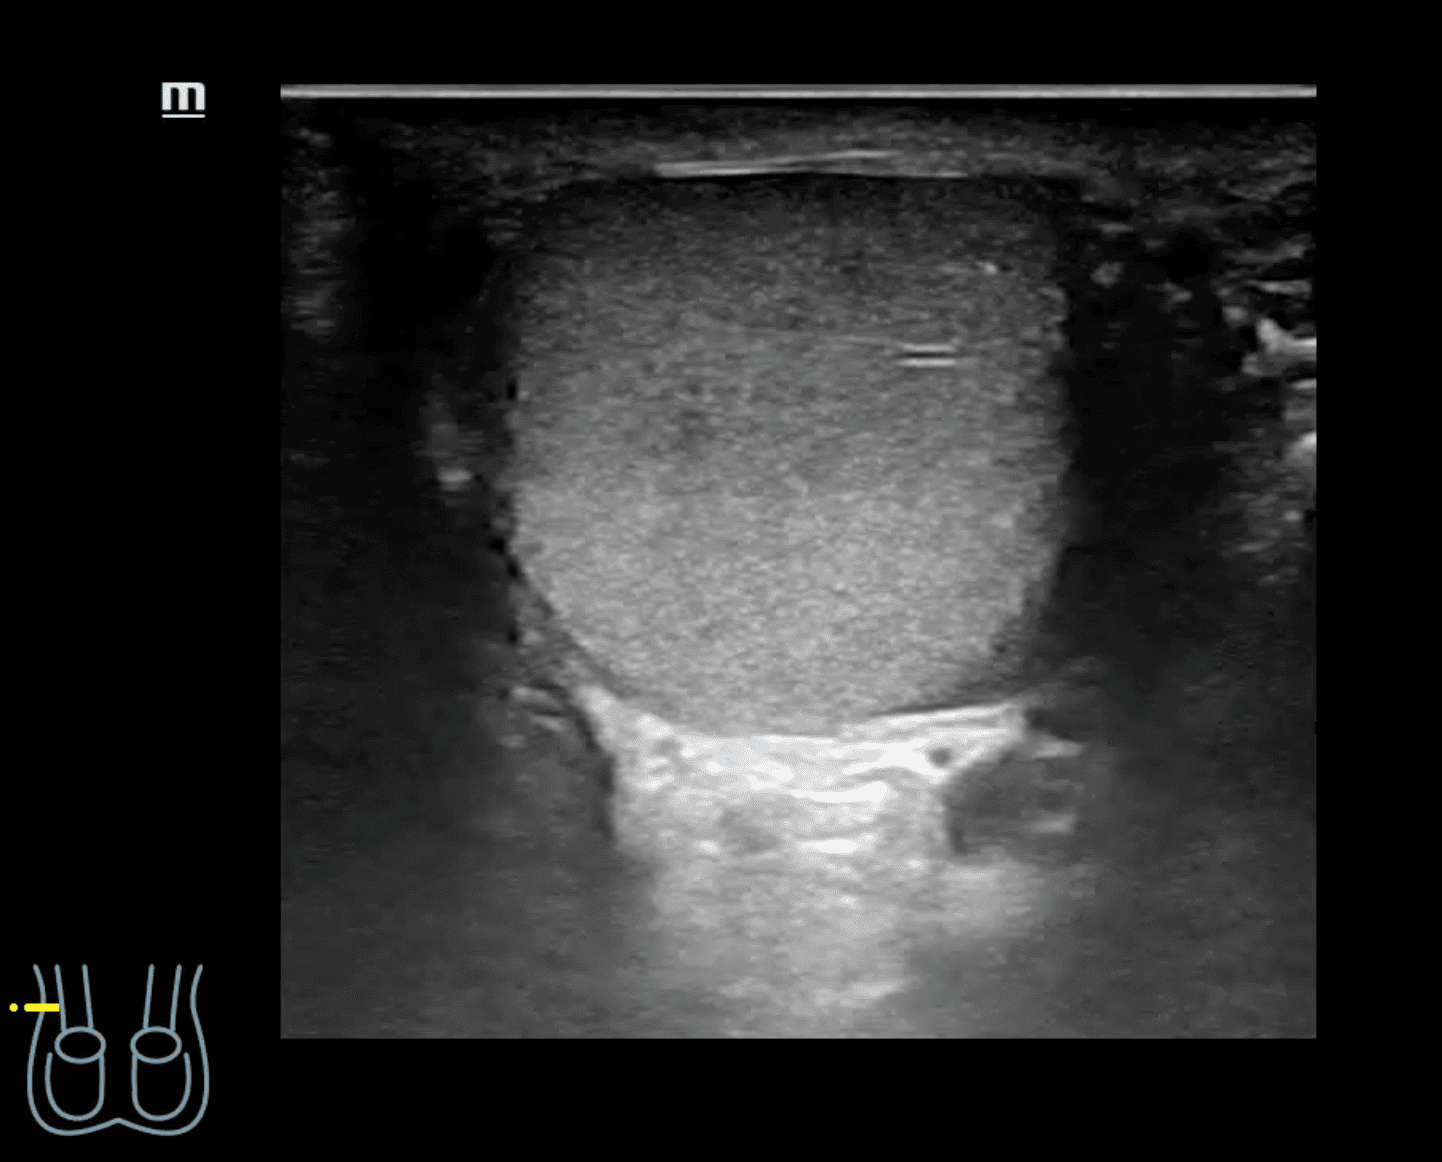

A nivel de escroto derecho, se observa imagen heterogénea con contenido intestinal compatible con hernia inguino-escrotal derecha. Testículos de aspecto normal.